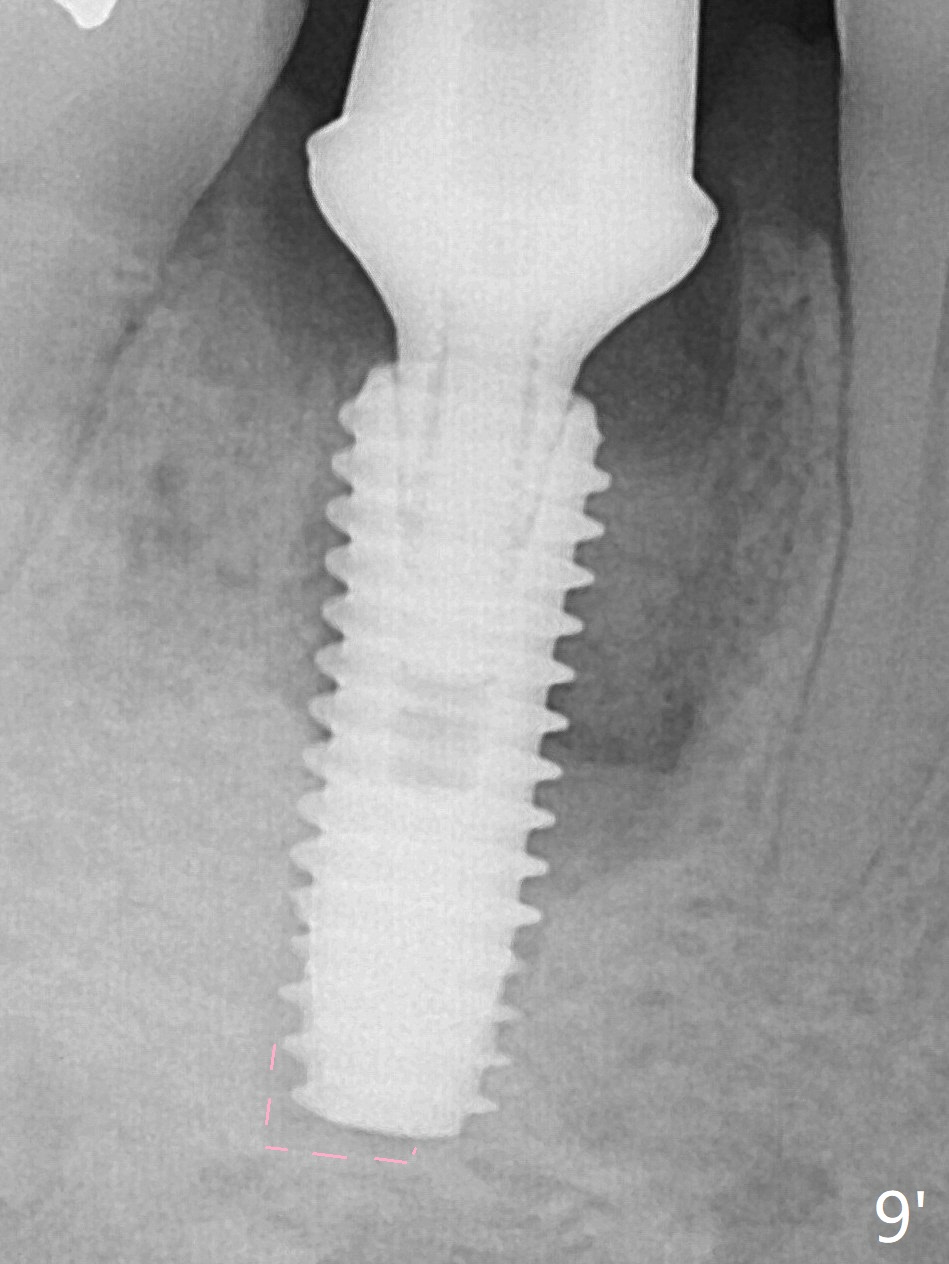

Preop oral Amoxicillin seems to be associated with reduction in the buccal and lingual (Fig.3 arrow) fistulae at #30, but there is mesiobuccal swelling (Fig.1 *) with 7 mm pocket (Fig.2). Osteotomy is initiated in the middle of the septum (Fig.3-5 S). As the osteotomy increases, it shifts mesially (Fig.6 arrow). Guided surgery is able to reduce shifting. A 5x13 mm implant is not seated completely (Fig.7) apparently due to osteotomy shifting. After removal of the bone from the osteotomy distally, the implant remains unseated with lower torque value (Fig.8). Following reuse of the 4.3 mm drill deeper by 1-2 mm, the implant is seated to a satisfactory depth (Fig.9 with increase in torque to 50 Ncm) with placement of Vera Graft (*) and a 7.5x4(3) mm abutment. After a second round of allograft placement (Fig.10 *), the implant is found to be 4 mm from the IAC. At the later stage of osteotomy, the coronal end of the septum is destroyed with loss of osteotomy depth landmark. It is apparent that the soft tissue landmark may be more reliable. The implant threads appear to be covered by the bone graft 3.5 months postop (Fig.11). The abutment is changed to 6.5x5(3) mm one before impression with minor margin prep. The bone density seems to increase 5 months postop, i.e., immediately post cementation (Fig.12) and 10 months postop (5 months post cementation (after retightening abutment), Fig.13 (*)). Periimplantitis develops mesiobuccally, consistent with bone loss 1 year 7 months post cementation (Fig.14 *); the implant seems to have been buccally placed. Bone graft is necessary with PRF or GEM21S if the vein is small and 6-month membrane with a hole around a 7.5x4(4) cemented abutment for easy wound closure. Take 5x5 CM CBCT to determine which wall has defect, buccal or lingual. Check mesial contact. If so, remove the crown, reseat the abutment (possible incomplete seating) and re-impress after bone graft.